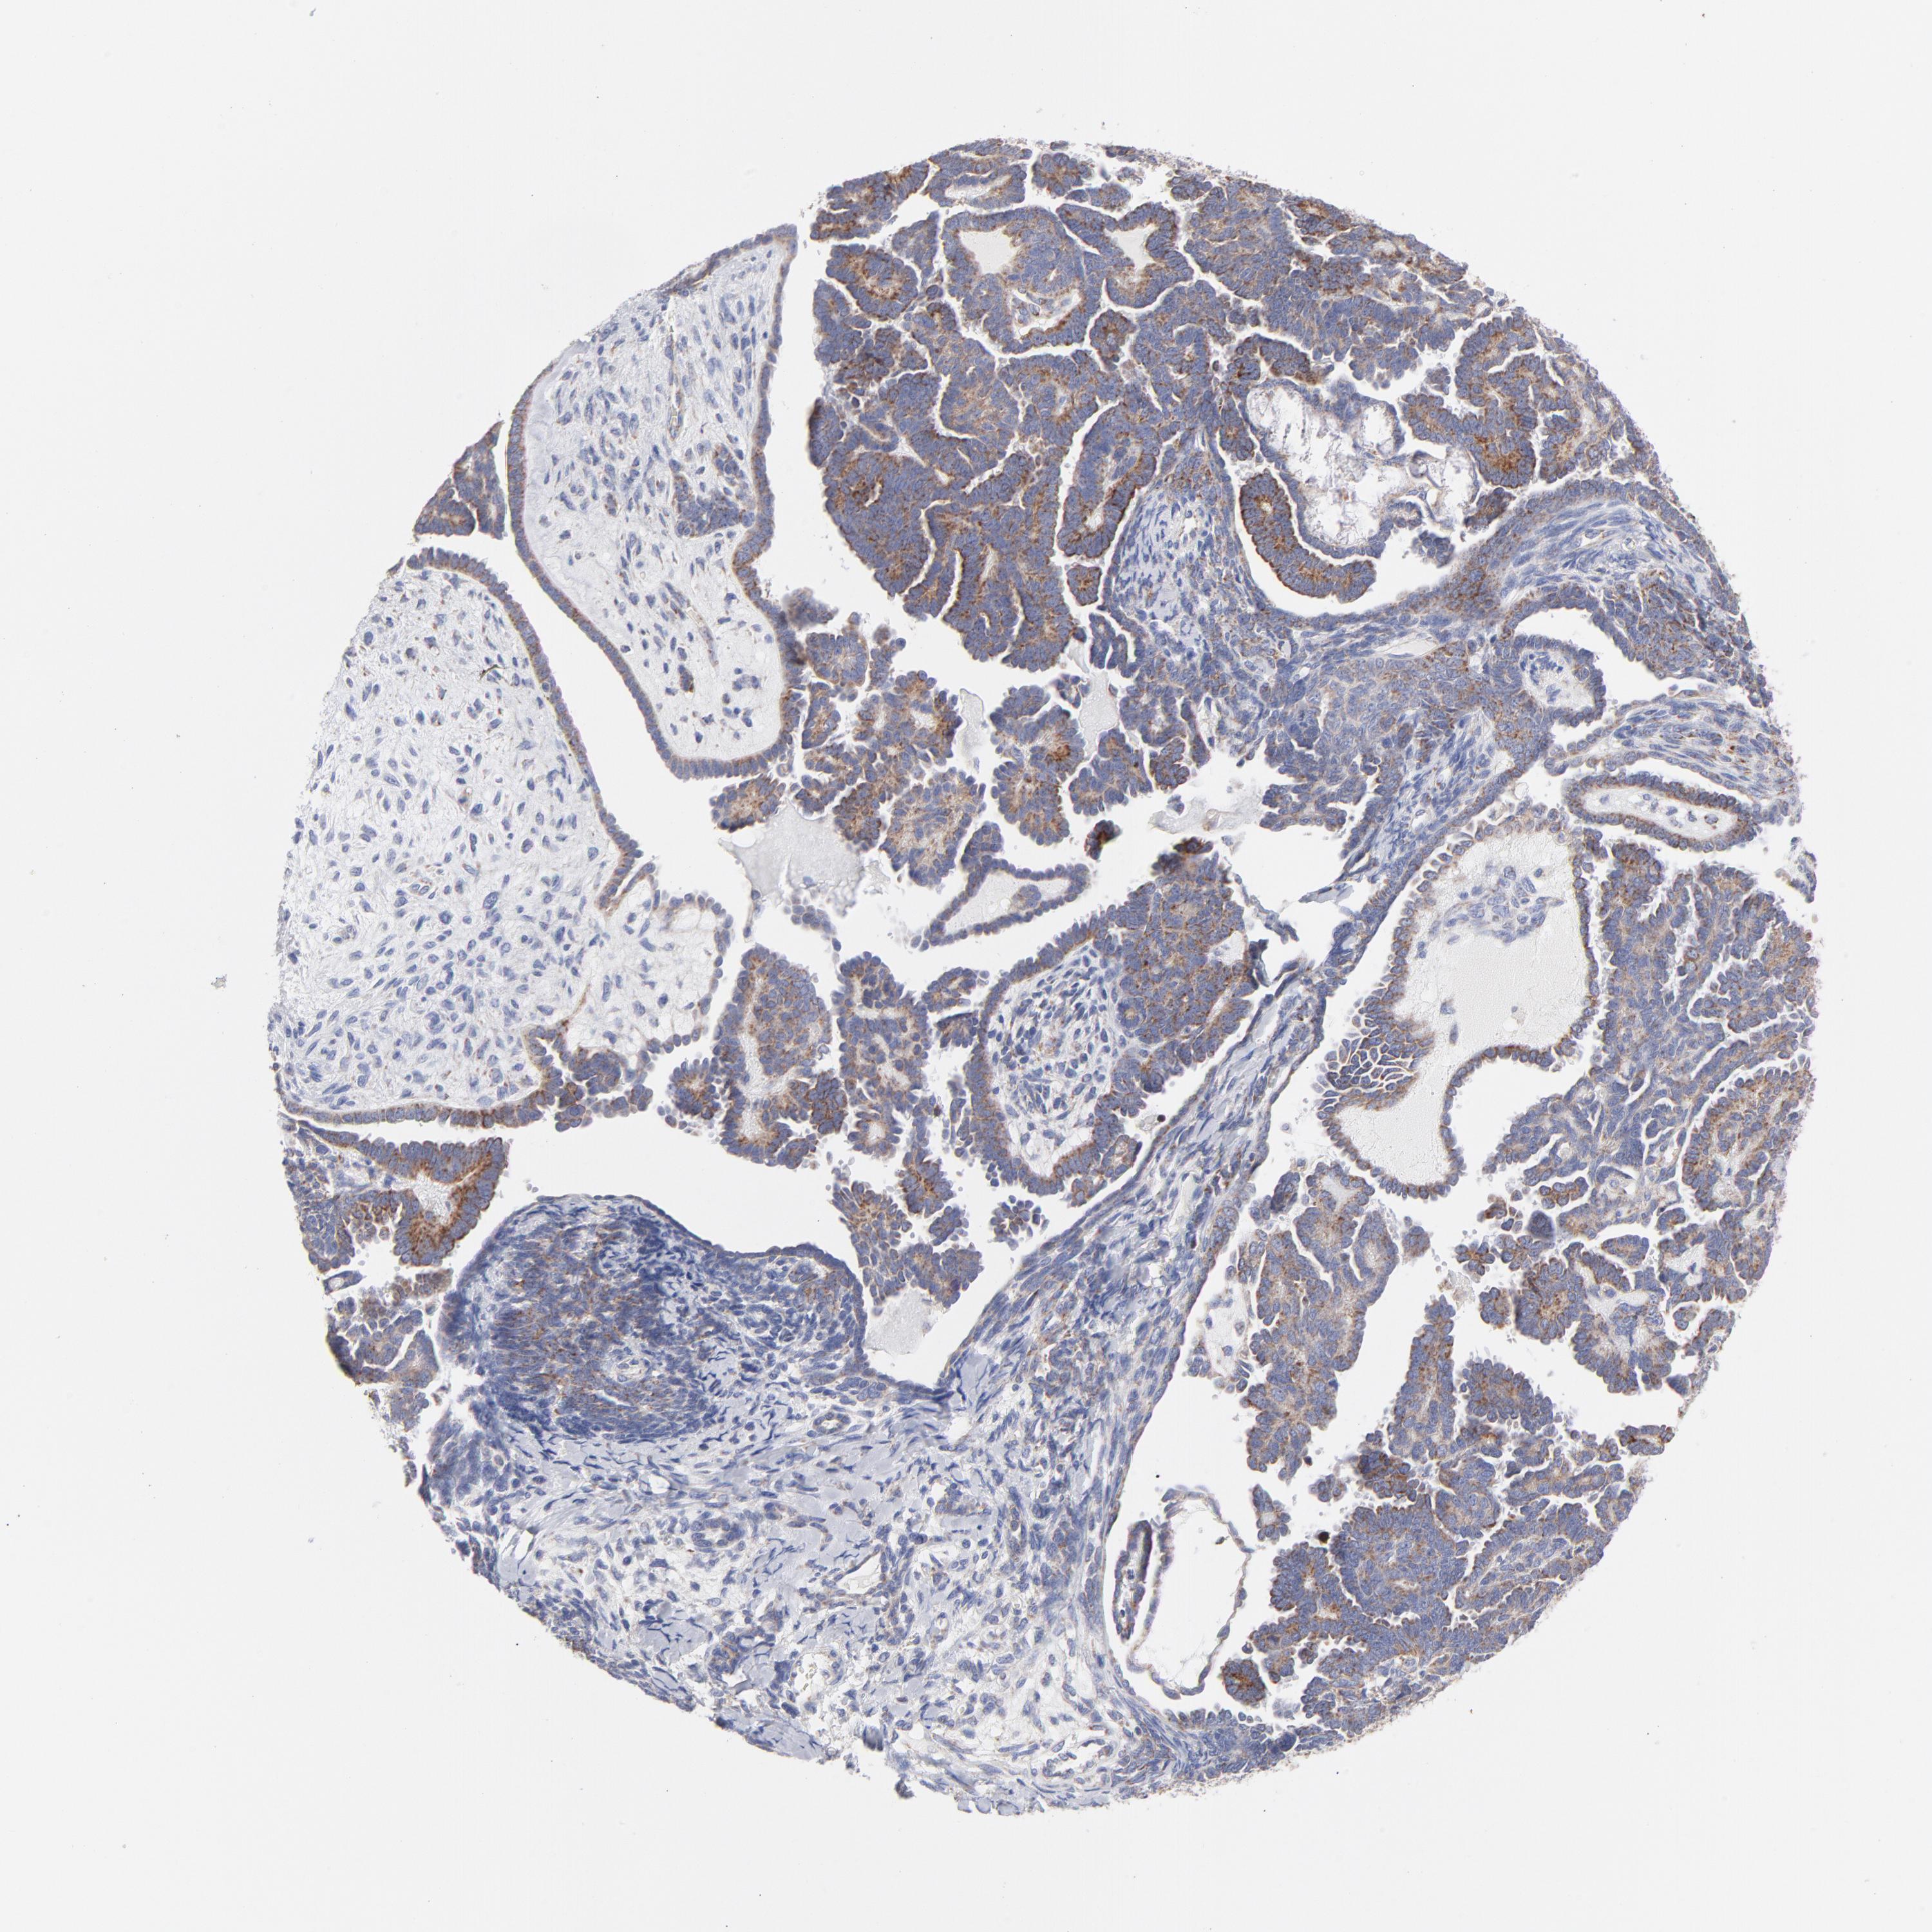

ENDOMETRIAL CANCER - Protein expressioni

A mouse-over function shows sample information and annotation data. Click on an image to view it in a full screen mode. Samples can be filtered based on level of antibody staining by selecting one or several of the following categories: high, medium, low and not detected. The assay and annotation is described here.

Note that samples used for immunohistochemistry by the Human Protein Atlas do not correspond to samples in the TCGA dataset.

Antibody stainingi

Antibody staining in the annotated cell types in the current human tissue is reported as not detected, low, medium, or high, based on conventional immunohistochemistry profiling in selected tissues. This score is based on the combination of the staining intensity and fraction of stained cells.

Each image is clickable and will lead to virtual microscopy that enables deeper exploration of all samples and also displays staining intensity scores, fraction scores and subcellular localization as well as patient and tissue information for each sample.

Antibody HPA003628

Staining

High

Medium

Low

Not detected

Intensity

Strong

Moderate

Weak

Negative

Quantity

>75%

75%-25%

<25%

None

Location

Nuclear

Cytoplasmic/membranous

Cytoplasmic/membranous,nuclear